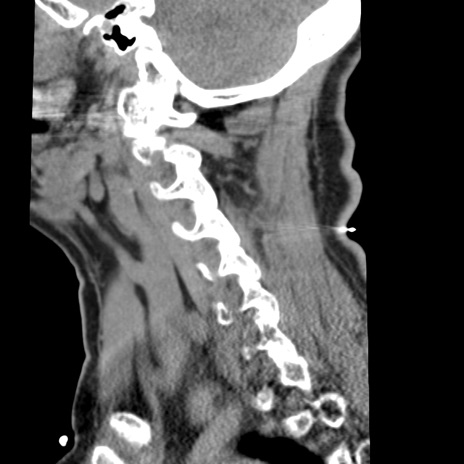

症例50 頚椎CT(矢状断像)

【症例】60歳代女性

【主訴】後頭部〜右後頸部にかけての痛み

【現病歴】本日飲食店でコーヒーを飲んでいたところ、突然後頭部〜右後頸部にかけて痛みが出現し、右上肢の感覚障害を伴ったため救急要請。

【身体所見】脳神経学的に明らかな異常所見を認めず。右上肢に軽度の感覚障害あり。

異常所見と診断は?

頚椎CT